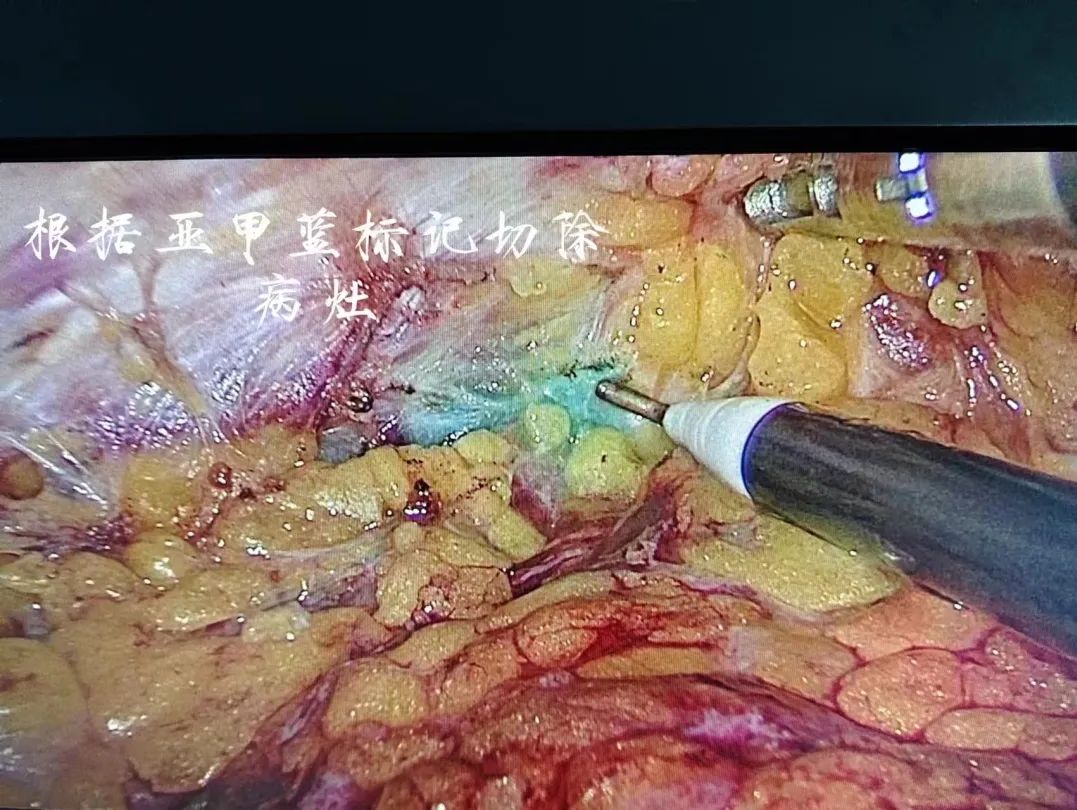

术前,用染色剂亚甲蓝在乳腺肿瘤边缘1cm环周注射标记好手术的切除范围内,仅取腋下皮纹3cm小切口,经此切口完成了前哨淋巴结的切除活检,以及腔镜辅助下完成肿瘤的切除,胸部不留任何疤痕。术后3天,苏女士顺利出院,患者及家属都对手术效果非常满意。